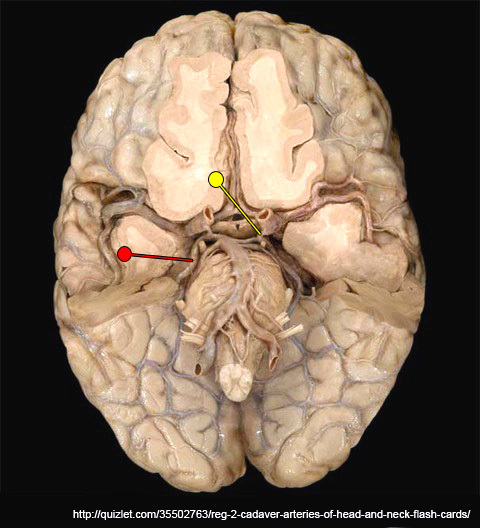

In the prosection illustrated below, vascular occlusion at the point indicated by the red pin would result in a lack of blood flow to which one of the following regions?

This is the posterior cerebral artery which supplies the medial occipital lobe of the cerebrum

In the prosection illustrated, vascular occlusion at the point indicated by the yellow pin would result in what change to blood flow to the cerebral hemisphere?

No change in the blood flow to the cerebral hemisphere